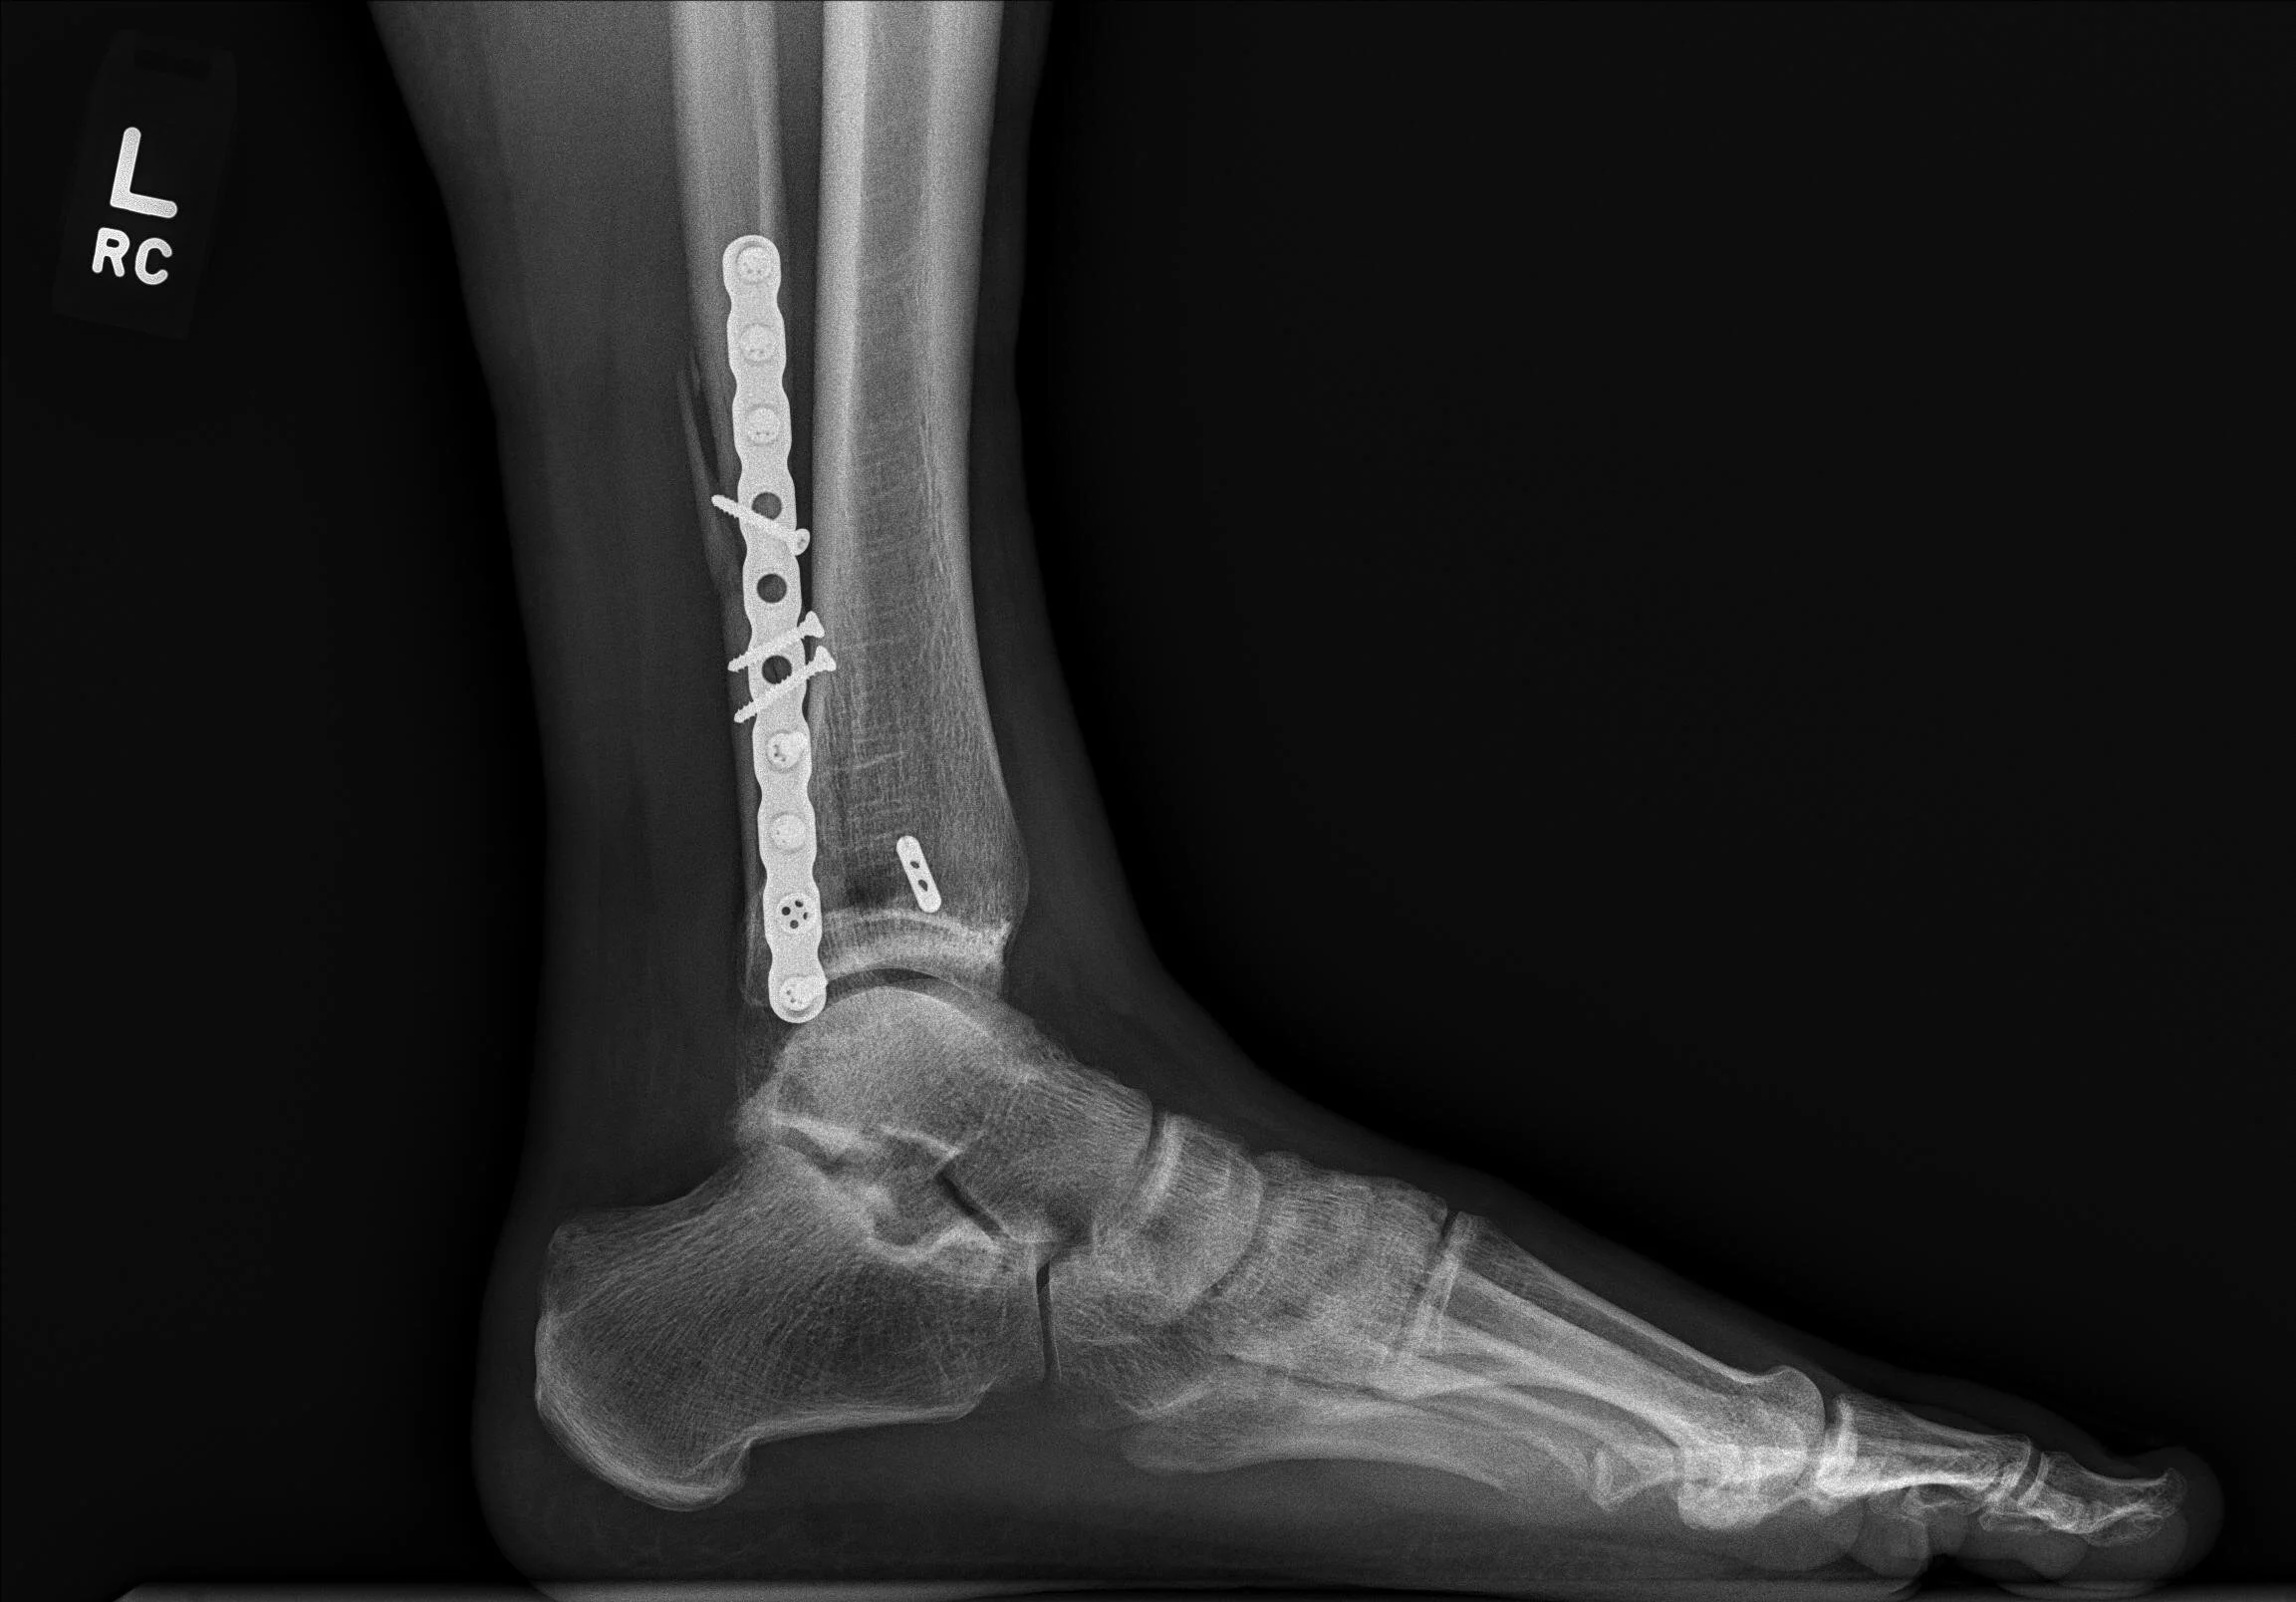

Surgery for fractures involves making an incision in the skin, putting the bones back into place, and keeping the bones in place using metal devices like plates and screws. In most cases, the metal can stay inside forever without issue.

Trimalleolar ankle fracture

Bimalleolar ankle fracture

Lateral malleolar ankle fracture with syndesmotic rupture